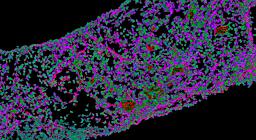

Pancreatic ductal adenocarcinoma is a lethal disease with limited treatment options and poor survival. We studied 83 spatial samples from 31 patients (11 treatment-naïve and 20 treated) using single-cell/nucleus RNA sequencing, bulk-proteogenomics, spatial transcriptomics and cellular imaging. Subpopulations of tumor cells exhibited signatures of proliferation, KRAS signaling, cell stress and epithelial-to-mesenchymal transition. Mapping mutations and copy number events distinguished tumor populations from normal and transitional cells, including acinar-to-ductal metaplasia and pancreatic intraepithelial neoplasia. Pathology-assisted deconvolution of spatial transcriptomic data identified tumor and transitional subpopulations with distinct histological features. We showed coordinated expression of TIGIT in exhausted and regulatory T cells and Nectin in tumor cells. Chemo-resistant samples contain a threefold enrichment of inflammatory cancer-associated fibroblasts that upregulate metallothioneins. Our study reveals a deeper understanding of the intricate substructure of pancreatic ductal adenocarcinoma tumors that could help improve therapy for patients with this disease.